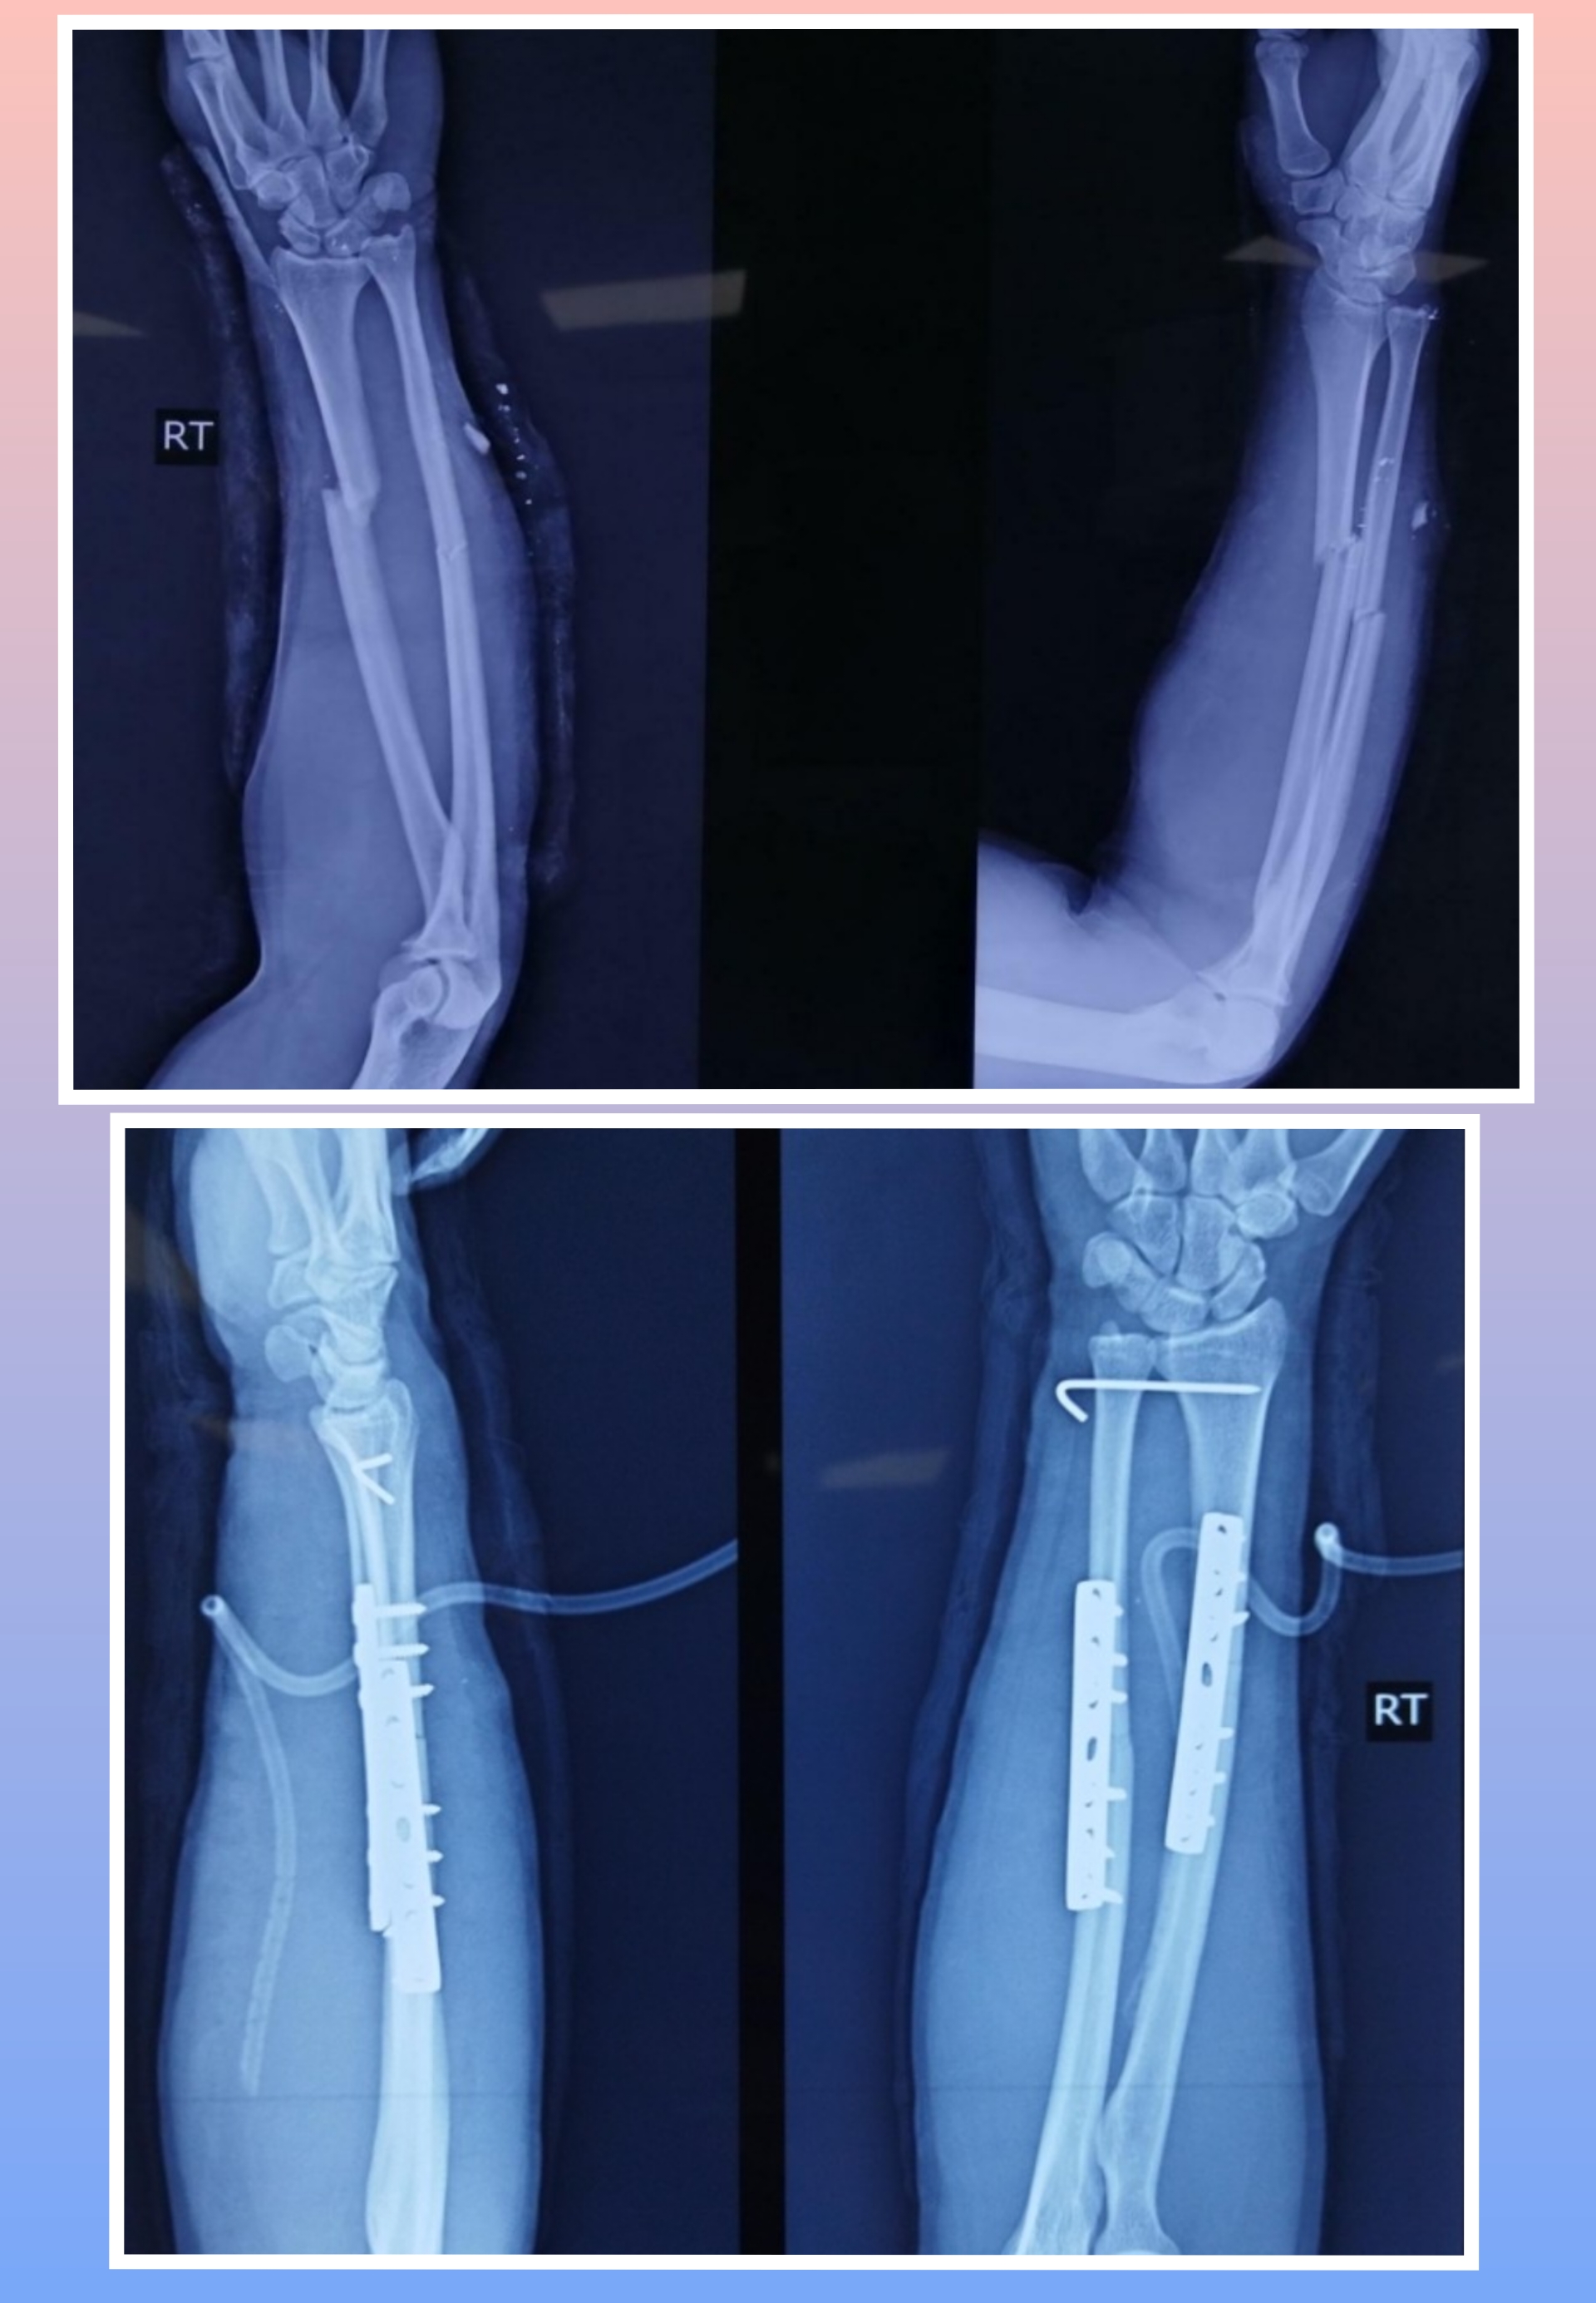

X-ray

Warning: Graphic Content

The following section contains graphic images of surgical procedures. These images are intended for educational purposes and may be disturbing to some viewers. Viewer discretion is advised.

Surgeries